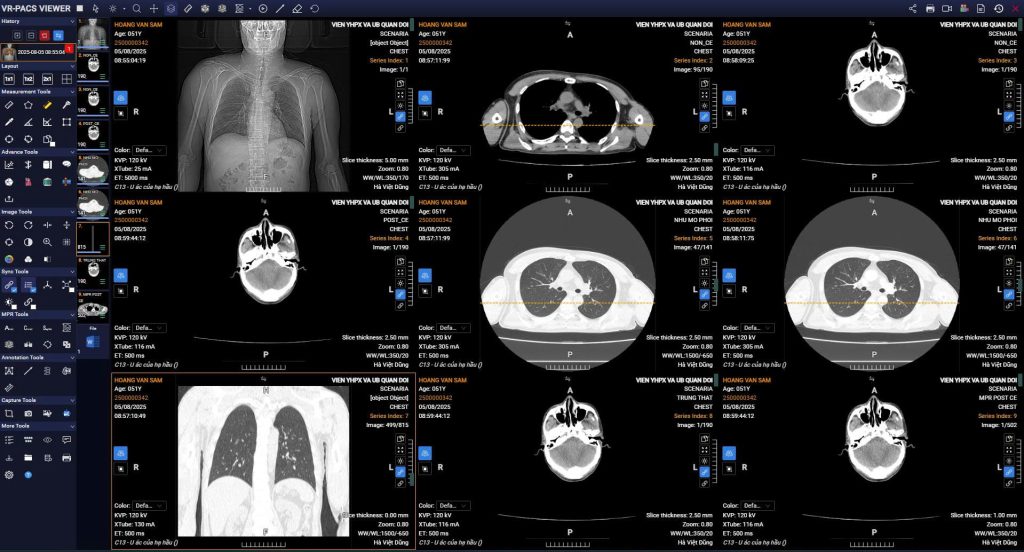

- Triển khai đồng bộ hệ thống phần mềm: HIS, LIS, RIS-PACS và phần mềm HSBAĐT, do Tập đoàn Viettel cung cấp, triển khai trên hạ tầng máy chủ đám mây.